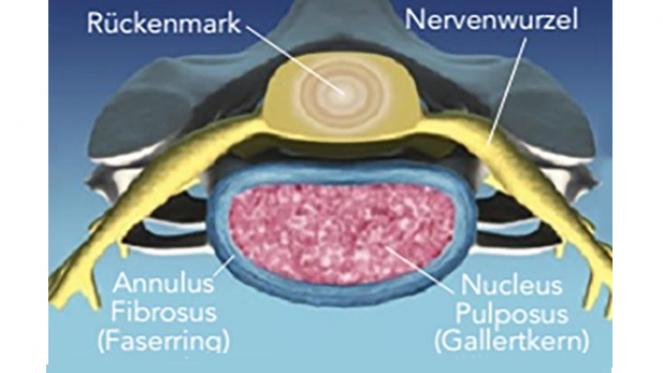

Bandscheiben sind flexible, faserknorpelige Verbindung, die als Stoßdämpfer zwischen den Wirbel dienen.

Mit zunehmendem Lebensalter kann es zu verschleißbedingten Rissen am äußeren Ring der Bandscheibe (Faserring) und zu einem Austritt des gallertartigen Kerns kommen. Dieser kann die benachbarten Nervenwurzeln oder das Rückenmark zusammendrücken und zu lokalen oder ausstrahlenden Schmerzen in den Armen und Beinen, ggf. auch mit Sensibilitätsstörungen und motorischen Ausfällen, führen.